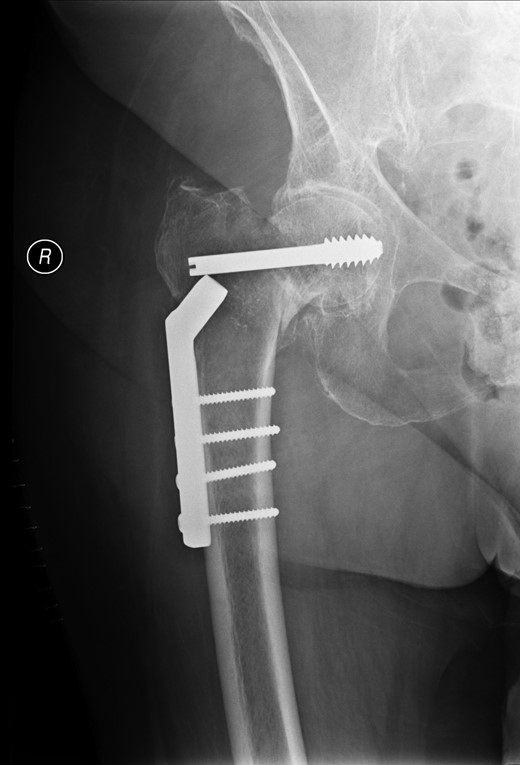

A lady of 88 years old presented with pain in her right hip following a fall at home. Radiographs of the proximal femur revealed an extra-capsular fracture, as shown in Fig. 1. She was taken to the operating theatre within 48 h. In an uncomplicated procedure, the fracture was fixed with a 75-mm, 135°, dynamic hip screw (DHS). A short (25-mm) barrel with four-hole plate was used. Intraoperative screening images are shown in Fig. 2. This position was accepted.

Review of the intraoperative radiographs (Fig. 2) shows that the barrel and screw are not properly engaged. Although the films may appear satisfactory at first glance, closer consideration reveals that the long axes of the barrel and screw are imperfectly aligned (Fig. 2). Following later experimentation on the bench with identical components, we discover that this is only possible when the length of overlap between barrel and screw is <3 mm. With such minimal overlap, the screw is resting on the lip of the barrel, yet is not fully engaged. In such a position, the screw cannot slide within the barrel. At overlaps greater than this, the screw and barrel cannot be other than coaxial.

Previous correspondents have explained the failure of the screw to slide within the barrel as a ratio of the length contained within the barrel, and the length protruding from it. In order to slide smoothly, without danger of binding, the length of screw protruding should be <4.7 times the length contained within the barrel [2]. This was not achieved here.

We hypothesize that the cause of failure was an intraoperative measurement error, leading to the selection and placement of a 75-mm screw, which was in fact of inadequate length. Thinking, however, that the selection was correct, the surgeon also chose to employ a short 25-mm DHS barrel following recommended practice from the literature [3]. This combination of components was too short to engage properly. Being improperly engaged, they were unable to slide as intended, and upon attempted mobilization by the patient, they immediately uncoupled the one from the other.

Intraoperative screening at the time of placement of the screw may concentrate on visualization of the proximal tip of the implant, to ensure that it occupies a satisfactory position in the femoral head and does not protrude into the hip joint. We stress that equal attention should be paid to the distal end, to ensure that it is correctly aligned with the barrel. Closer scrutiny of the intraoperative screening films for evidence of the appearance described above could have identified this avoidable complication, the resolution of which required major revision surgery.